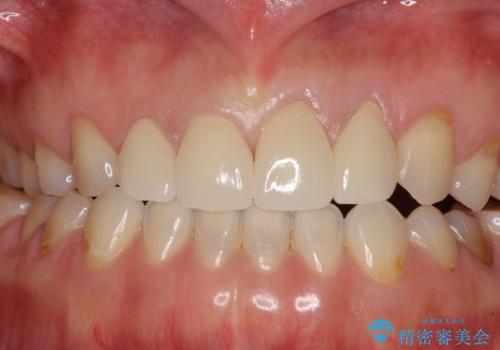

口元への目線ばかりを気にしていた状態から、自然な口元へと変貌し、患者様には大変満足していただきました。

4本の前歯が気になっていたので、全てをオールセラミッククラウンにて補綴治療を行うこととしました。

4本とも治療前の歯髄の状態は正常でしたが、補綴治療により歯を大きく削ることになるため、歯髄が炎症を起こすリスクがあることを了解いただきました。